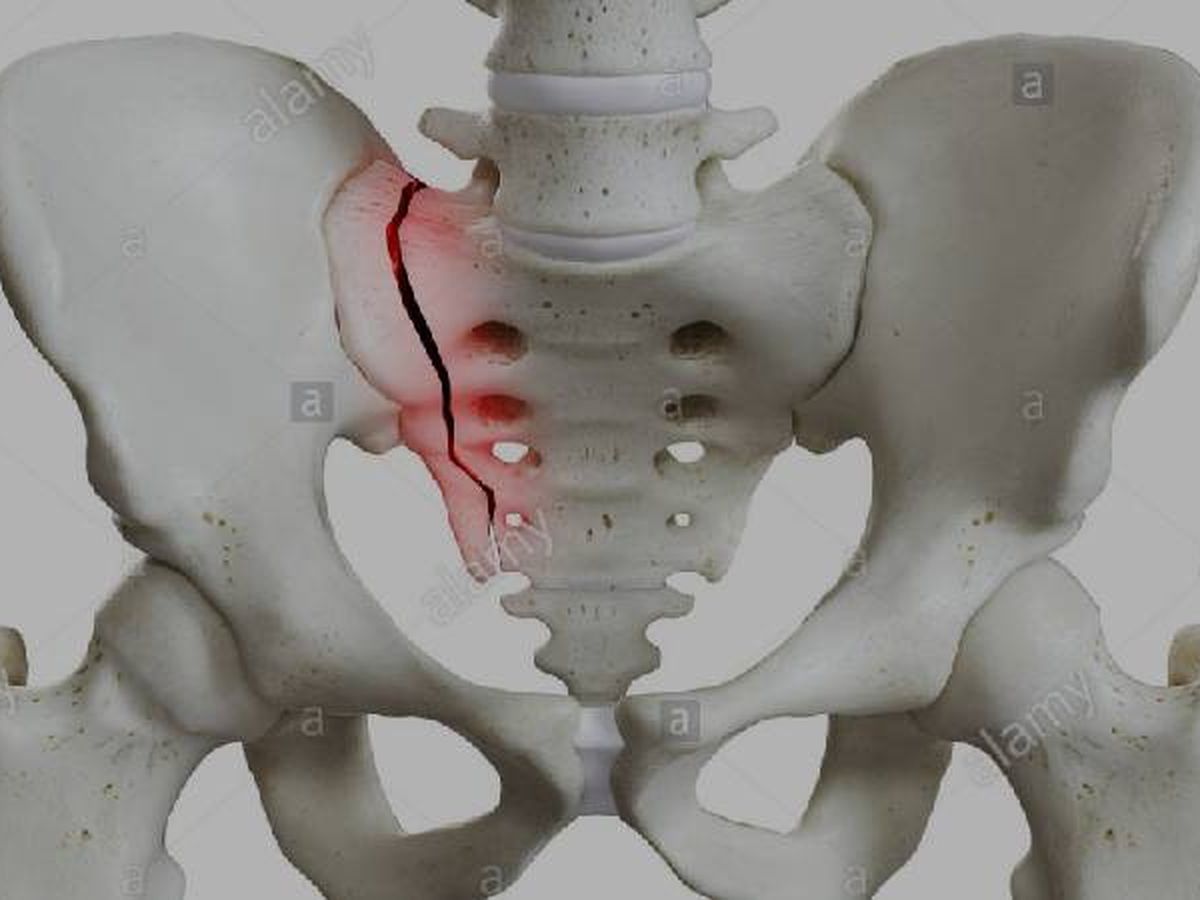

Hey everyone i absolutely hate asking for handouts but im not sure where else to turn. As most of you know I broke my pelvis about a month ago. The medical bills are piling up and i need to pay upfront to see a orthopedic surgeon to make sure it hasnt become displaced and need surgery. Anything you can do to help even just sharing is greatly appreciated.